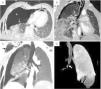

Our patient was a 50-year-old man with multiple injuries. Chest CT with intravenous contrast agent identified laceration of the intermediate bronchus (Fig. 1).

Chest CT with intravenous contrast agent: (A) Axial plane, lung window. Fallen lung sign (dashed white arrow) due to collapse and displacement of the pulmonary hilum toward the lower segments. Right tension pneumothorax (white asterisk) is also observed, causing contralateral mediastinal displacement and pneumopericardium (dashed black arrow). (B) Coronal reconstruction, lung window. Pneumomediastinum with air surrounding the bronchi and pulmonary vessels lying in parallel to bronchi in the pulmonary hilum (black arrowhead). (C) Multiplanar reconstruction with minimum intensity projection, coronal plane, lung window showing subcutaneous emphysema (solid black arrow) and airway discontinuity (white arrow). (D) Three-D volume rendering, anteroposterior projection with suppression of right lung. Laceration of the intermediate bronchus with bronchial amputation and discontinuity of the airway (white arrow).

Bronchial ruptures are typically parallel to the cartilaginous rings, less than 2.5cm from the carinal angle, and are slightly more predominant in the right side.1,2 Indirect signs, such as pneumomediastinum and cervical emphysema, can be seen on imaging tests. Persistent pneumothorax, refractory to drainage tube placement, occurs if the lesion reaches the pleural space. CT has a fundamental role, allowing direct identification of airway discontinuity, angulation, and bronchial defect or amputation. If the rupture is complete, the lung can collapse and fall away from the hilum toward the lower segments (“fallen lung sign”).1

Multiplanar reconstructions CT images with minimal intensity projection are useful if tracheobronchial injury is suspected. Bronchoscopy can confirm the diagnosis and assess its extension. Early surgery should be performed to attempt primary repair.1,2